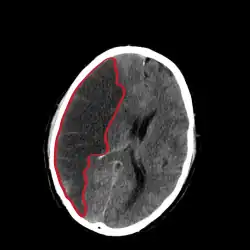

CT scan slice of the brain showing a right-hemispheric cerebral infarct (left side of image). | |

Computed tomography (CT) and MRI scanning will show damaged area in the brain. A CT scan will rule out a hemorrhagic stroke, is cheaper for the patient, and can be found in almost all hospitals unlike an MRI machine.[26][27] Once the Doctor rules out a hemorrhagic stroke, rTPA can be given.[26] An MRI can help to diagnose an acute cerebral infarct as quickly as 6 hours from start of symptoms,[26] It can also help time when the stroke happened.[28] The biggest problem with an MRI is it cannot be done on a patient with certain metallic implants or if the patient is claustrophobic.[29] A head and neck CT angiogram can be performed within 6 hours of onset of symptoms to see where the occlusion may be located which can help in determining the cause of the stroke.[30] In people who die from a stroke an autopsy can reveal additional diseases or conditions beyond the stroke itself, as well as uncover uncommon causes of a stroke.[31]